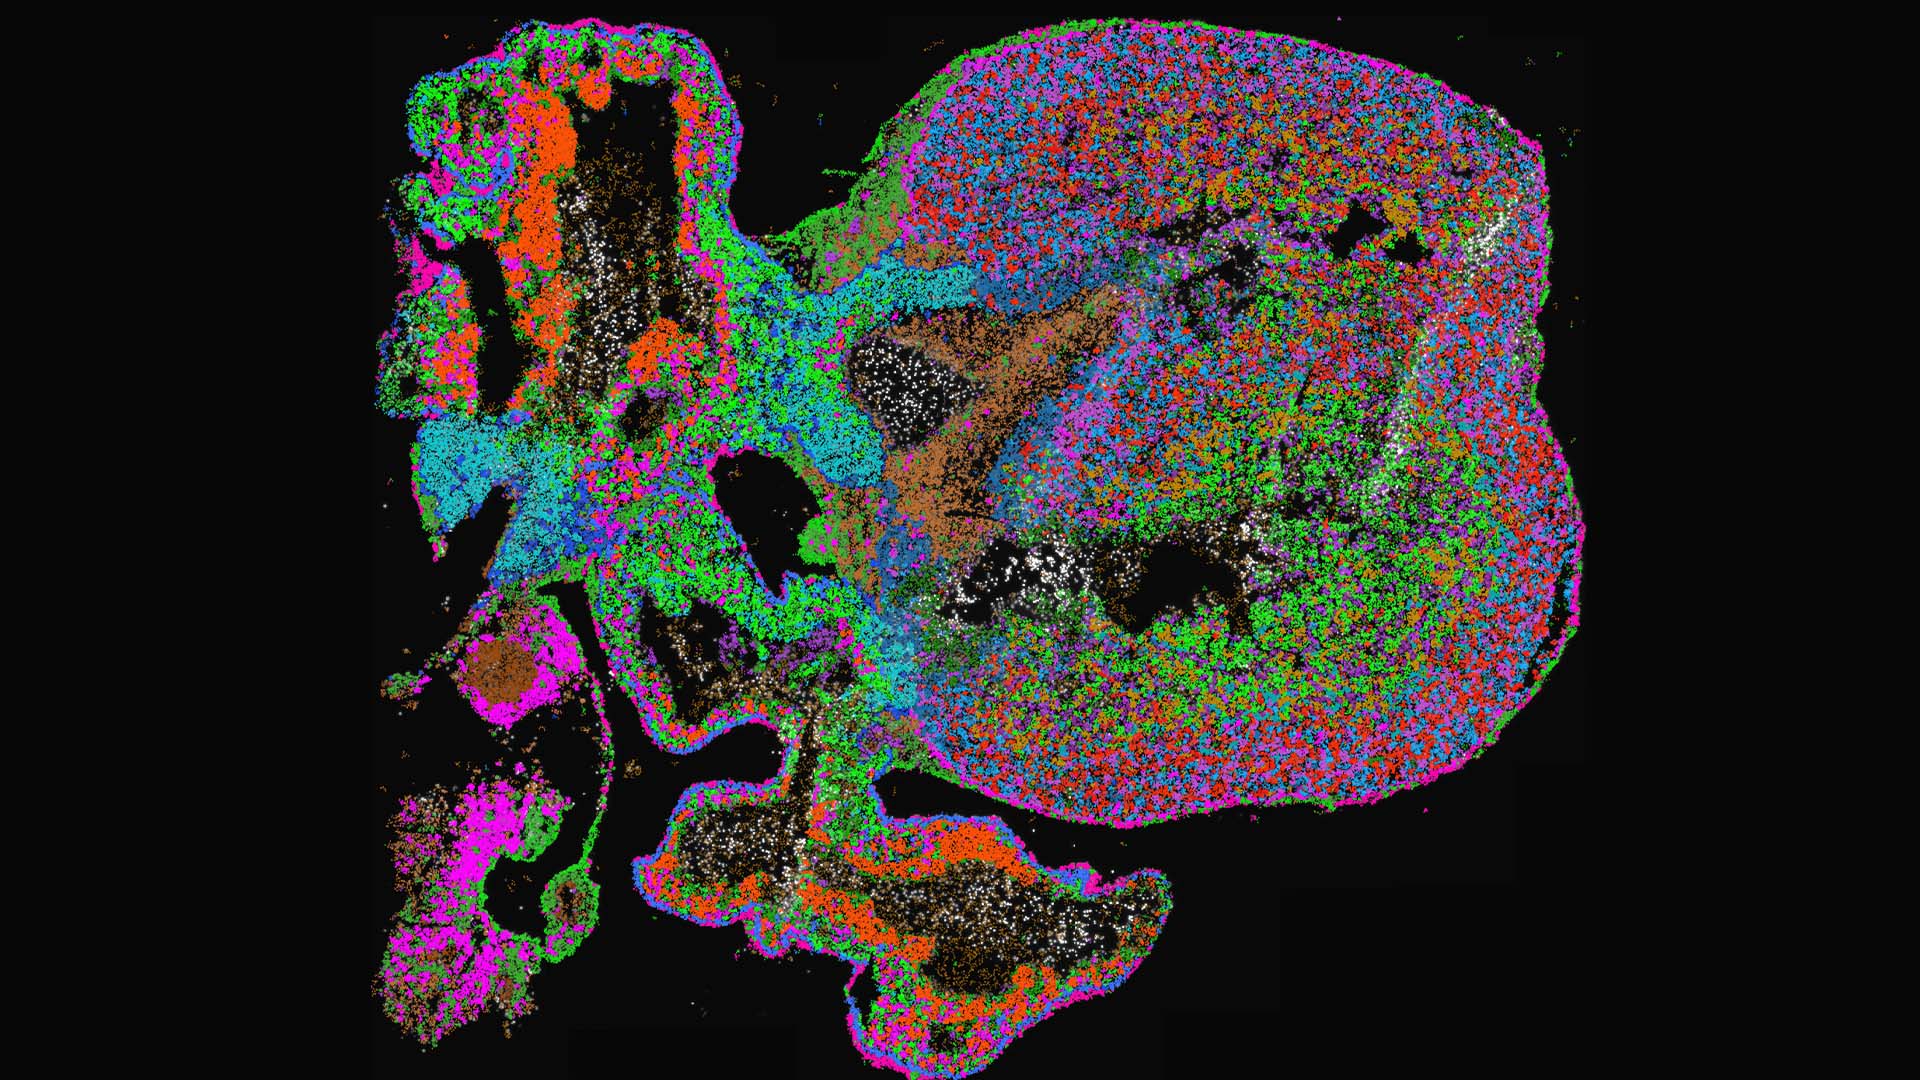

SciLifeLab researchers have for the first time utilized graph neural networks to characterize cellular diversity of in situ sequencing data, during human heart development. The study provides a useful resource for online exploration of cell-type differentiation during heart development at sub-cellular image resolution.

The researchers obtained and made accessible well-defined spatial cell-type maps of fetal hearts from four and a half to nine post-conception weeks.